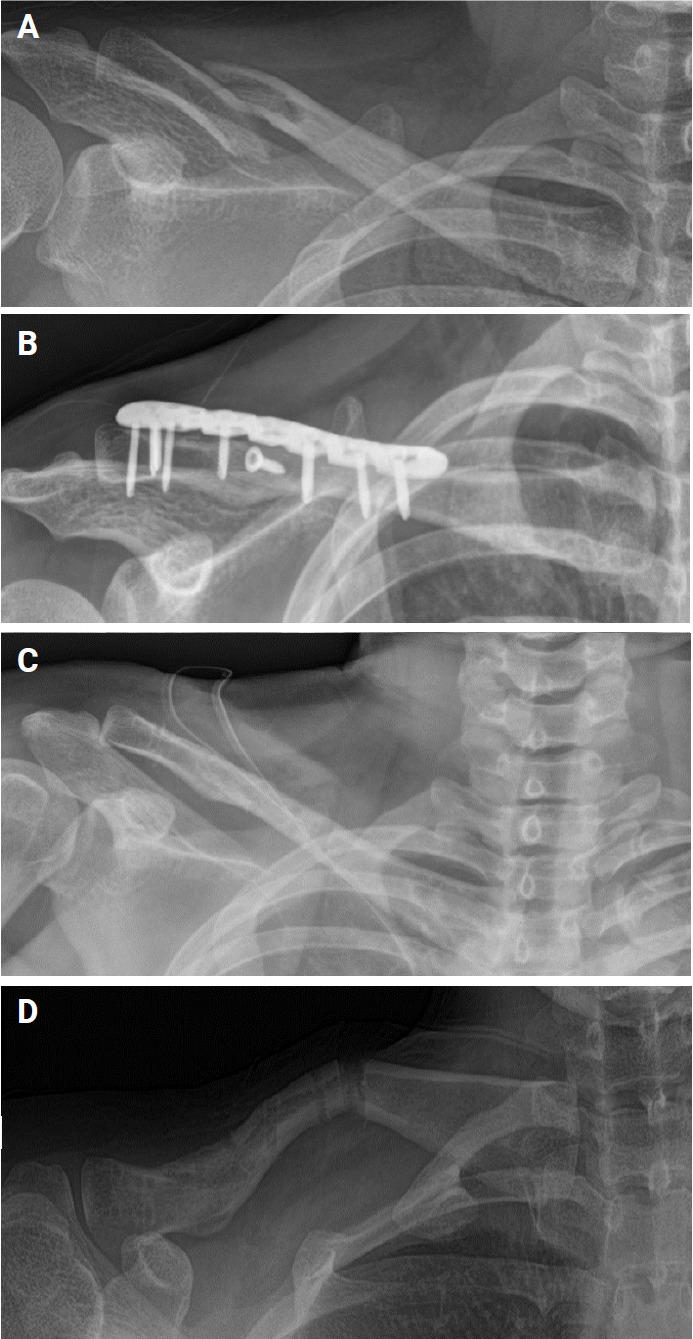

Background: This study aimed to compare the outcomes and complications of active young adults undergoing open reduction and plate fixation (ORPF) and intramedullary nailing (IMN) for displaced midshaft clavicle fractures (MCFs).

Methods: A retrospective review was performed on all patients undergoing ORPF and IMN of complete MCFs at a single center between 2018 and 2022. Patients who were younger than 60 years with radiographic follow-up until union were included in the study. The mean age of the patients was 33.1 years. Outcome measures were achievement of union, time to healing, residual deformity, complications, and need for additional procedures.

Results: Of 39 patients, 29 underwent ORPF and 10 underwent IMN. Plate fixation provided faster functional recovery in the first 6 months, but no difference was observed after 1 year. All fractures in the IMN group healed (100%), compared to 90% in the ORPF group (P=0.08). Mean time to union was 21±8.9 weeks and was significantly different between the two groups (P<0.01), with the ORPF group averaging 23.1 weeks and the IMN group 20.8 weeks. Nonunion rates were higher in the ORPF group (10.3%) than in the IMN group (0%), but the difference was not significant (P=0.08).

Conclusions: Both methods restored patients to their pre-injury functional levels. However, IMN, with its higher healing rate, fewer required revision surgeries, and lower incisional numbness, appears to be the preferred method for treating MSFs without comminution in young adults. Level of evidence: III.